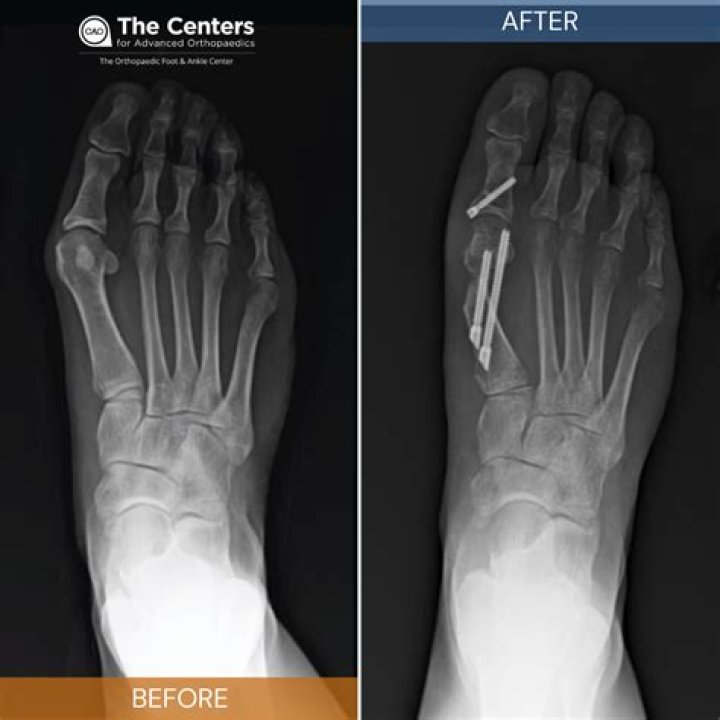

Does bunion surgery require screws?

Bunion surgery most often involves an incision in the top or side of the big toe joint and the removal or realignment of soft tissue and bone. This is done to relieve pain and restore normal alignment to the joint. Small wires, screws, or plates may be used to hold the bones in place.

Are pins used in bunion surgery?

Osteotomy: Your surgeon makes a few small incisions in the bones. Then the surgeon uses screws or pins to realign your big toe joint. This is the most commonly performed procedure for bunions.